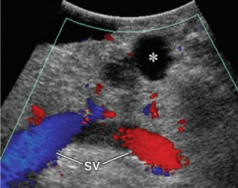

Describe this image

Dx?

A small, well-defined, hypoechoic, cystic lesion located in the body of the pancreas towards the tail end.

Dx: most likely a cystadenoma